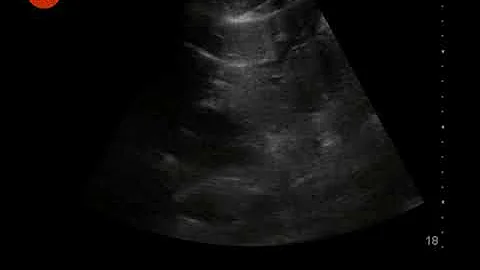

Step by Step instructions on Performing IVC Ultrasound in the Easiest way Possible!